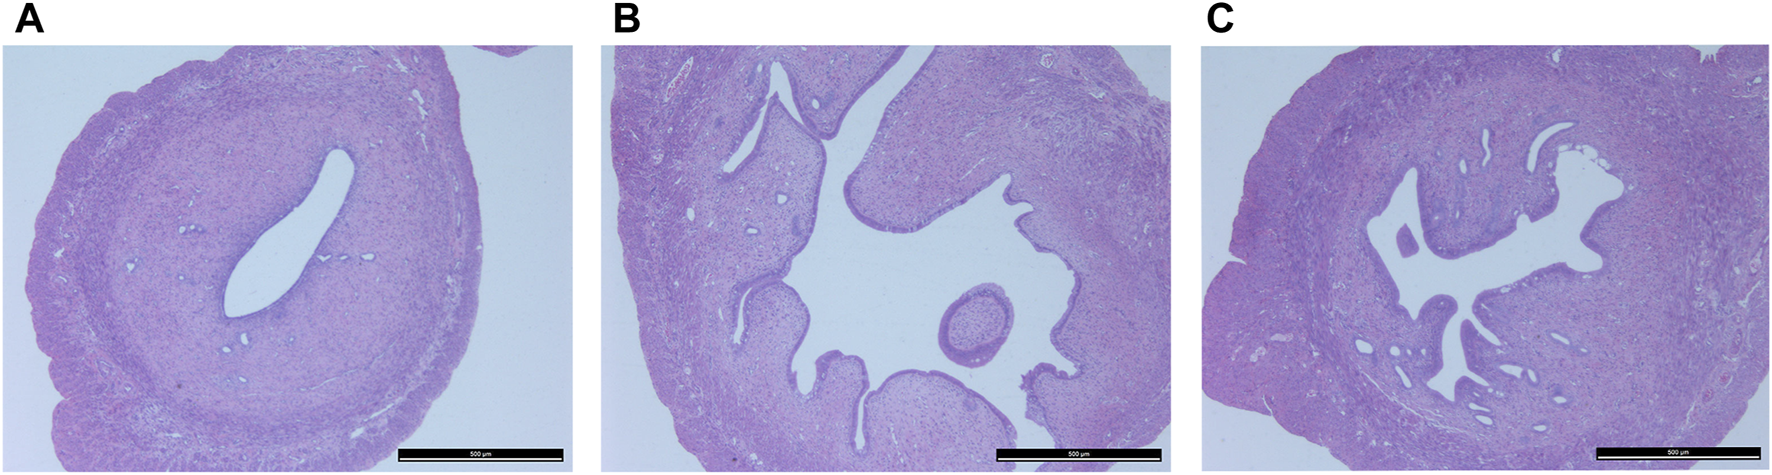

Figure 3 shows histopathological sections of the uterus. In the control group, endometrial epithelial cells are complete, the thickness of endometrium and myometrium is normal, and uterine cavity is smooth. However, in the model group, the uterine structure is out of order, uterine cavity is not smooth and the endometrial hyperplasia is obvious. The uterine cavity of the Guizhi Fuling group tends to be smooth. Figure 4 shows typical pathological sections of the rat ovary. For ovarian tissue, the follicles of the control group are arranged in an orderly manner. While in the model group, the number of atresia follicles increases, the arrangement of follicles is disordered, after the treatment of Guizhi Fuling, the symptoms above are relieved. As shown in Figure 4D, compared with the control group, the corpus luteum radius of the model group increased by about 1.5 times, and the corpus luteum radius decreased by about 1.2 times after administration of Guizhi Fuling.

FIGURE 3

Histopathological section of uterus(A) Control group (B) Model group (C) GZFL group.